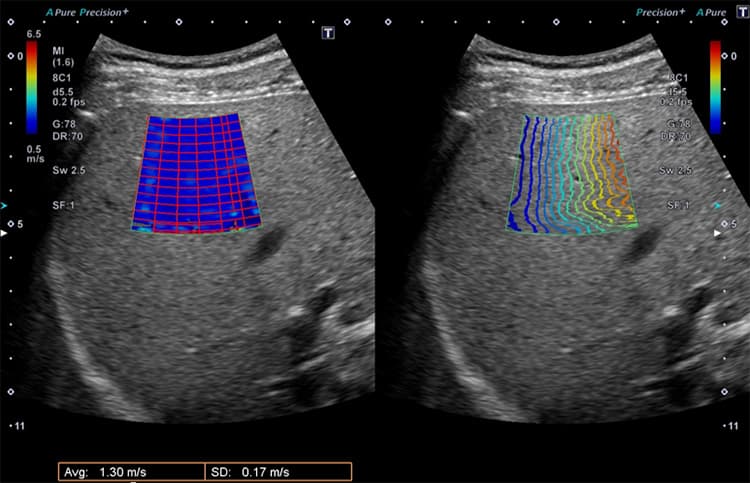

SWE(肝臓の硬さを評価)

SWE(Share wave Elastography)は、肝脂肪化および肝線維化(肝臓の硬さ)を評価し、脂肪肝の進行状況とリスクの有無を推定します。従来、肝線維化の診断には腹部に針を刺す「肝生検」が主流ですが、SWEでは針を刺す必要がないため、検査に伴う負担が少なくなります。

当院ではATIとSWEでの診断を併せて用いることで、より正確に脂肪肝を診断してまいります。